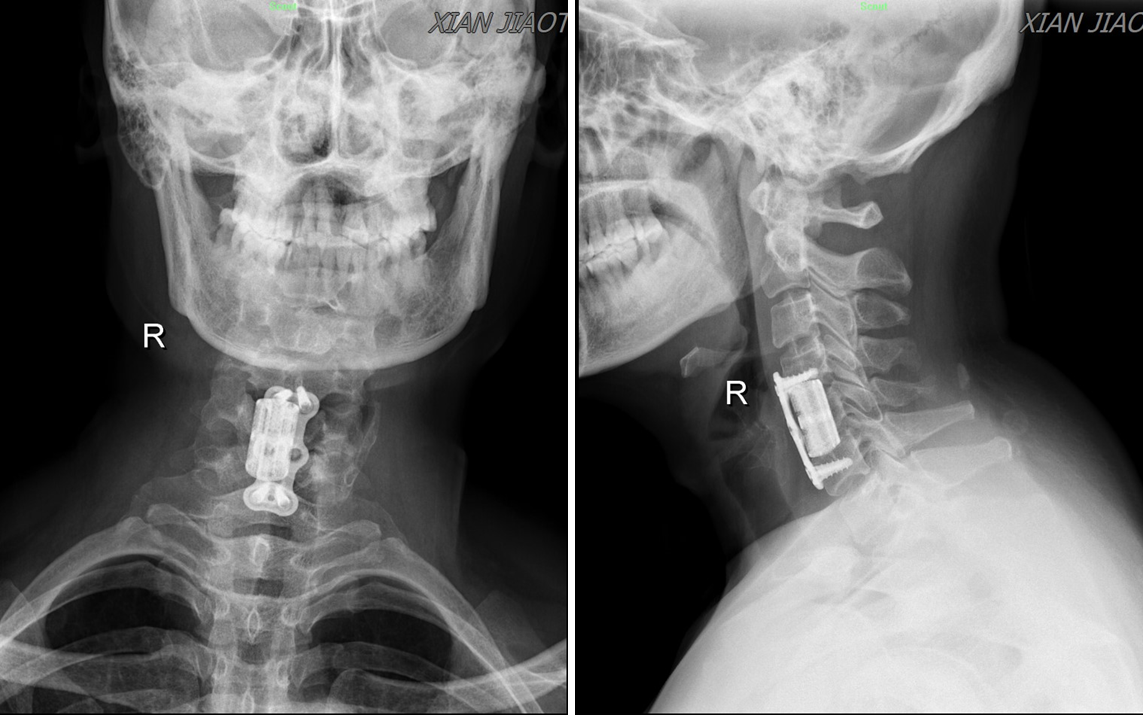

图4术后颈椎正侧位片

来自陕西省渭南市的许某被头晕症状折磨了8年之久,犯病时伴有濒死感、心慌、胸闷、气短、大汗,偶尔伴有耳鸣及听力减退等症状,十分痛苦。反复就诊于不同级别的医院,要么被误诊为颅内疾病、冠心病、或高血压等疾病,结果治疗无效;要么确诊为颈椎病,但因未接受手术治疗,导致症状反复无法缓解。1月前患者怀着忐忑的心情就诊于我院神经内科,展淑琴主任团队快速给患者完善了颅脑MR 3T平扫、头颅MR血管成像、颈部MR增强血管扫描等专科检查,均未见明显异常(图1),考虑该患者头晕可能与颅内疾病关系不大,于是联系耳鼻喉科、骨科中心骨病与创伤病区等多学科会诊。张纯主任通过详细询问病史、认真查体后初步考虑该患者头晕可能系颈椎病所致,并嘱患者完善颈椎MRI及颈椎正侧双斜位片检查进一步确认。经过仔细查阅加拍的影像学检查,张纯主任发现,患者颈4/5、颈5/6椎间盘突出严重,相应椎管狭窄;最为重要的是颈椎双斜位片上左侧颈5/6钩椎关节增生明显(图2),且从MRI轴位片上可以看到椎动脉在颈5/6层面存在受压(图3),于是向患者告知病情,并果断建议其手术治疗。患者饱受头晕困扰,鉴于张纯主任每次交流中均展现出的专业素养和工作态度,患者毫不犹豫地选择手术治疗,遂转入骨科中心骨病与创伤病区。经过骨三科护理团队专业的术前准备和医生团队详细的术前规划,在麻醉团队、手术护理团队的保驾护航下,张纯主任主刀,高宗强主任医师及李永伟博士协助,为患者实施了颈椎前路椎管减压术,术中张纯主任仔细操作,反复检查椎动脉减压效果,直至减压满意。术后3天给与患者复查术后X线片,显示非常满意(图4)。患者下地活动后发现头晕症状完全缓解,出院后1周还特地与张纯主任取得联系,告知“现在一点都不晕了”。医生的专业判断、果断决策及精准手术,加之患者的高度配合,使得手术得以顺利、成功进行。